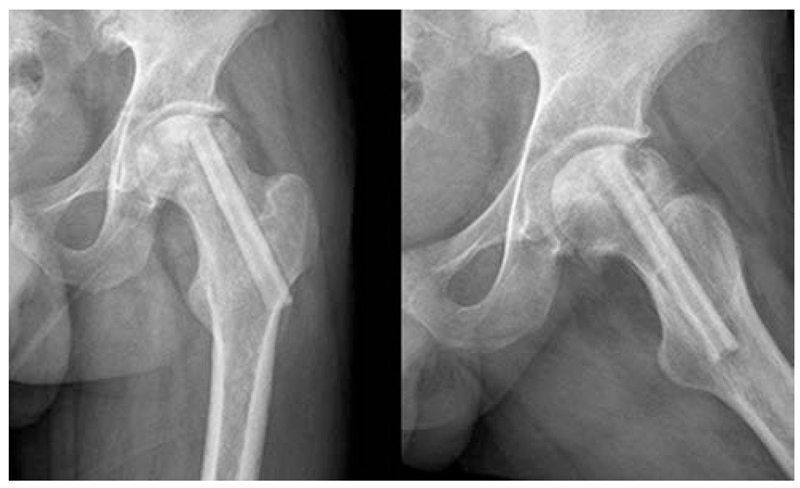

3、多孔细(Multiple CD,MCD)髓芯减压术

为了克服单孔髓芯减压术的缺点,科学家们进行了改进,采用细针进行多孔道的髓芯减压,通过以直径为3-4mm的克氏针代替传统钻头,进行多方向多孔道的减压MCD和SCD相比,可到达更多的坏死区域,减压更彻底,手术创伤更小。由于对股骨头、股骨颈处结构影响小,保留孔道之间的支撑结构,因此股骨头塌陷、骨折等并发症发生率也更低。

2004年,Mont首次报道多孔径技术对股骨头坏死塌陷前FicatⅠ期患者2年随访,其成功率为80%。2008年,David研究表明,多孔径髓芯减压术组较传统髓芯减压术组,可适应坏死分期更高。文献报道在坏死范围较小者,失败率在14%-25%,坏死范围较大者,失败率达42%-84%。

一项研究显示,多孔径适应证主要限于Ficat分期Ⅰ、Ⅱa和Ⅱb,但也包括一些Ⅲ期的年轻病人,长达11年的随访,163个关节中的108个(66.3%)最后一次随访时被认为是临床上成功的。在108个被认为是临床成功的髋关节中,34个在随访期间出现了额外的塌陷。74个关节(45.4%)被认为达到了放射学和临床成功。

2016年Brown也认为,经皮多孔径随芯减压术(MCD)较传统单孔芯减压术(SCD),有更少软骨损害及转子下骨折及容易操作等优势,但临床疗效相近,不管是SCD还是MCD,在减压后股骨头修复的过程中,骨吸收的速度往往较新骨的形成快,使本薄弱的软骨下骨的机械支撑力进一步减弱从而更易引起股骨头塌陷,塌陷率仍有30%左右,患者仍需拄拐下地或限制活动。